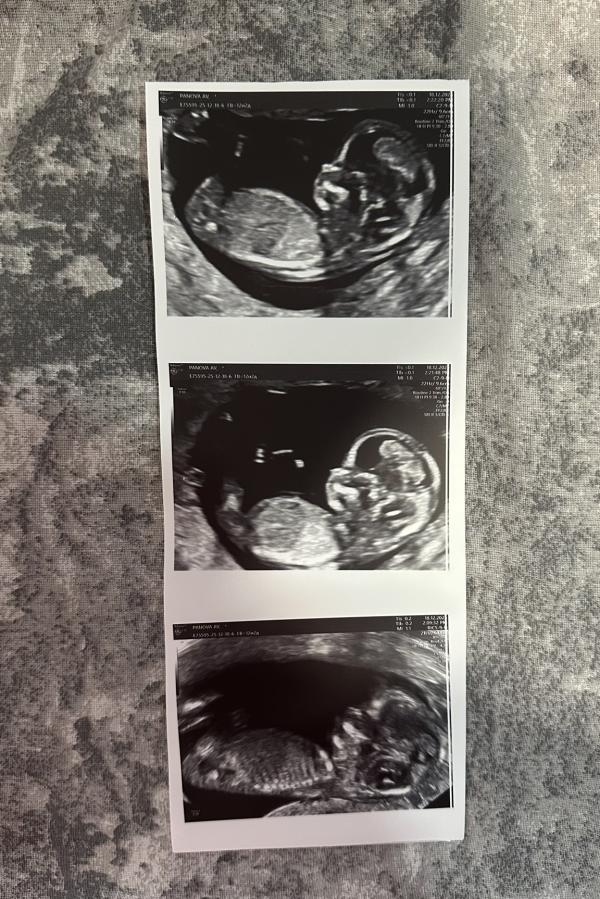

После этой ужасной жк №1 и Ивановой. Наревелась и поехала в «Саико», несмотря на то что там была полная запись и некоторые специалисты на больничном меня согласилась взять глав-врач Щетнева Ольга Александровна. Сделали фетометрию. Какая же замечательная женщина, все показала, рассказала, я в кабинете была наверно минут 40 если не больше, пыталась подлезть, повернуть малыша, разбудить чтоб сфотографировать. Я сняла все на видео, увидела ручки, ножки, пальчики. И даже пол смогли увидеть да так отчетливо что просто без сомнений.

У нас будет мальчик🩵

@nastekpanova, да у вас там пиструнчик будь здоров 😂 даже я близорукая вижу 😂